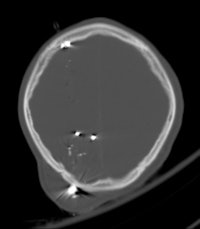

Plain radiography and CT are the most commonly used modalities for imaging of gunshot wounds, but angiography and MRI are playing an increasing role, according to research presented at the 2011 U.K. Radiological Congress (UKRC) in Manchester.

Doctors involved in the care of these patients need to understand the patterns and mechanisms of the injuries, he explained. To accurately interpret images of gunshot wounds, a basic knowledge of ballistics is important, especially the factors affecting the extent and type of tissue damage. Such knowledge is useful not only for evaluating acute injuries but also for determining the path of the missile, awareness of missile fragmentation, and embolization, thus contributing to the overall clinical, and often the forensic, picture.

The two mechanisms of tissue injury that account for the majority of damage caused by a bullet are direct crushing of tissue by the projectile (causing a permanent cavity) and temporary cavitation, which stretches and tears surrounding tissues. Increased velocity, fragmentation, deformation, and rolling/spinning of the bullet will cause more damage by both these mechanisms, he pointed out.